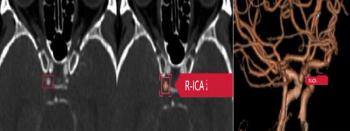

Emphasizing the proper diagnostic characterization of sidewall aneurysms, the authors of a new study found no significant differences in occlusion status or complications when they compared the approved use of intrasaccular flow disruption for bifurcation aneurysms to off-label treatment of sidewall aneurysms.

A recent study found that Viz ANEURYSM had a 94 percent accuracy rate of diagnosing subarachnoid hemorrhages on computed tomography angiography (CTA).

Researchers say the complementary use of artificial intelligence may significantly improve the accuracy of radiologists in diagnosing intracranial aneurysms.